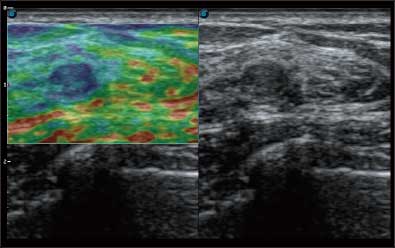

通过对组织运动信息、血流信号及背景噪声进行准确智能的阈值判定,高效提取出微弱血流信号,获得高灵敏度和空间分辨率的血流图像,为临床提供更加真实和丰富的诊断信息。